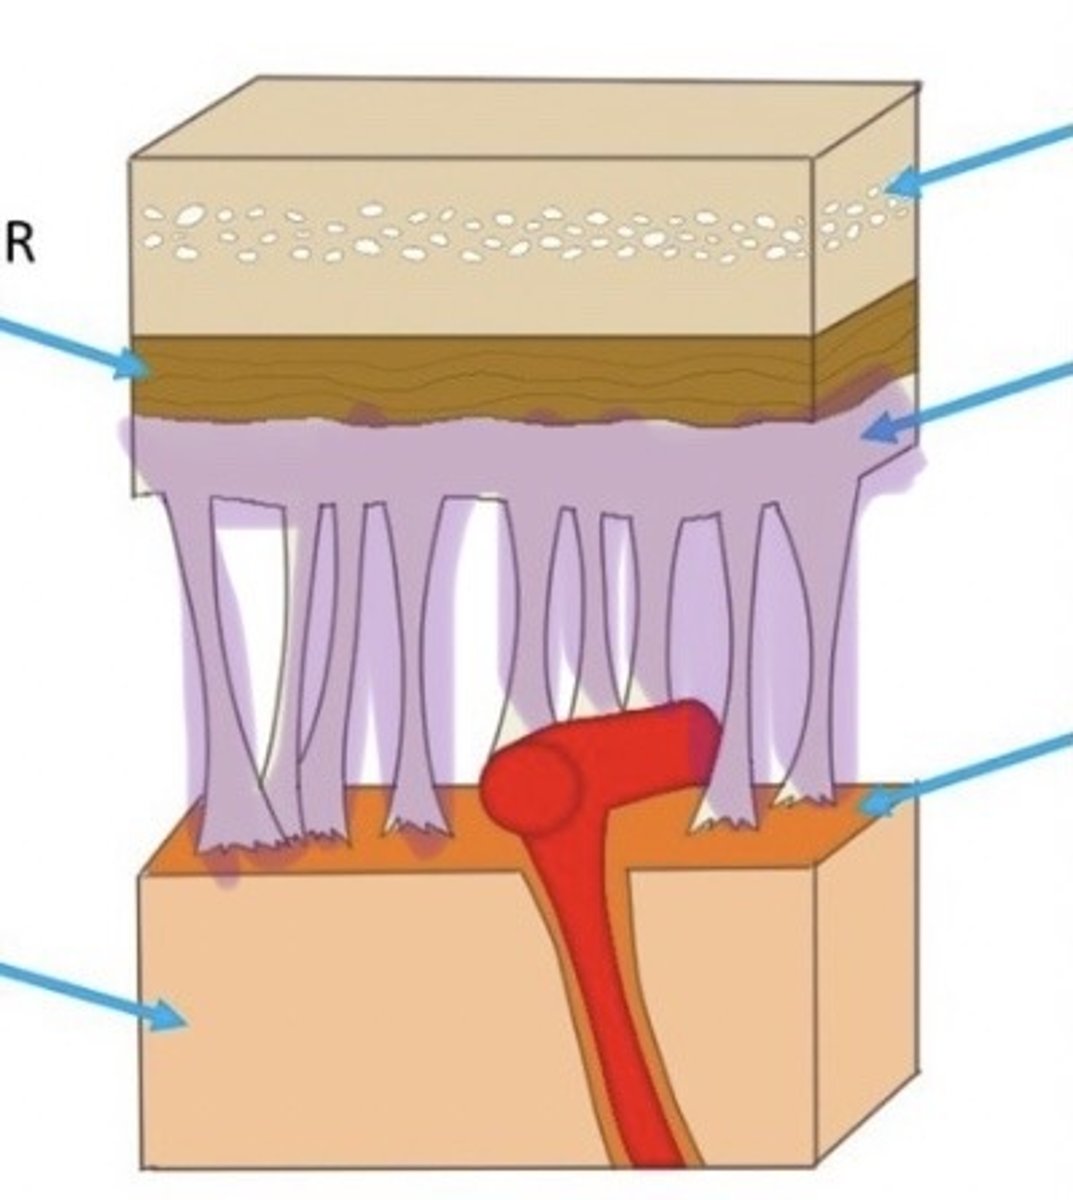

Meninges

The three protective membranes

-dura mater

-pia mater

-arachnoid

Dura Mater

Arachnoid Mater

Pia Mater

Sheep Dura Mater

this is a thin, cotton-like connection between the dura & pia mater, this is dissolved in the preservative & not visible in the brain we dissect

Arachnoid layer in Sheep